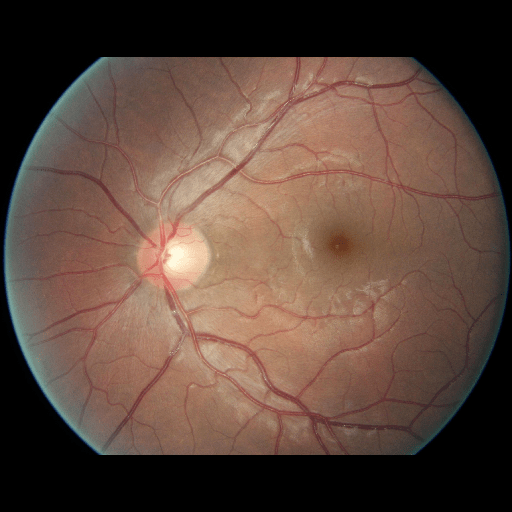

We conducted a case study on diagnosing diabetic retinopathy with ensembles of DL models. For benchmarking the performance of our ensemble-based solutions under the scheme described in Sec.3.3, we used two popular collections of diabetic retinopathy image data, the Kaggle Diabetic Retinopathy dataset [22] (hereafter referred to as “Kaggle-DR”) and the Messidor-2 dataset [23], each respectively consisting of and high resolution images. Diabetic retinopathy is graded into five SLs, as displayed in Figure 2. Following the problem setup used in previous papers [24], we trained models to distinguish the referable (SL2-4) cases from the non-referable ones (SL0 & SL1) (see Section B.1 for more detailed descriptions). We also tested our trained ensemble models on two o.o.d. image datasets (ImageNet [25] and CIFAR-10 [26]) to examine their capabilities of identifying o.o.d. inputs (see Section B in the supplementary materials).

5.1 Distribution of Uncertainty Scores

Distribution of Uncertainty Scores Across Different Severity Levels As explained in Section 3, each uncertainty metric essentially defines an order/ranking among the data points. We conducted an analysis to better understand what data will be assigned high uncertainty under a particular uncertainty metric . Picking out the highest ranked data points (), we calculated the ratio of data points from each SL. Figure 4 summarizes the results as box plots for the Kaggle-DR and the Messidor-2 datasets; additional detailed statistics can be found in Table S.1 in the supplementary materials. From the plot and table, SL1 & SL2 examples account for a higher proportion among the top-ranked uncertain examples across the three ensemble methods. This finding matches our intuition that incipient disease examples (SL1 & SL2) are more likely to be considered uncertain by ensemble methods due to their ambiguity.

The Kaggle-DR dataset comprises high resolution images. The presence of diabetic retinopathy is rated into five different SLs: no-DR (SL0), mild (SL1), moderate (SL2), severe (SL3), and proliferate (SL4), as illustrated in Figure 2. We divided the Kaggle-DR dataset into a development set and a test set, which respectively consisted of and images. The data in the development set were used to train and validate our Deep Learning (DL) models. The Messidor-2 dataset [38] that consisted of images was also used in our experiment as an additional dataset to test the true generalization performance of the models trained on the Kaggle-DR dataset. Images in Messidor-2 dataset were graded into the five SLs as in the Kaggle-DR dataset. Figure S.1 provides an illustration of the datasets used in our experiments.

The image data used in our experiment were all unified into square-shaped images with resolutions or in our preprocessing procedures. For training each neural network model, only images of the same resolution were used. The original images came with either of the two forms as exemplified in Figure S.2. In the first form (Figure 2(a)), the entire fundus was visible in the image. We cropped the image such that the fundus was tightly fitted inside the square. In the second form of input images shown in Figure 2(b), part of the fundus was not visible. We padded blank strips to make the image square-shaped and in a unified resolution. See the provided code for further details.